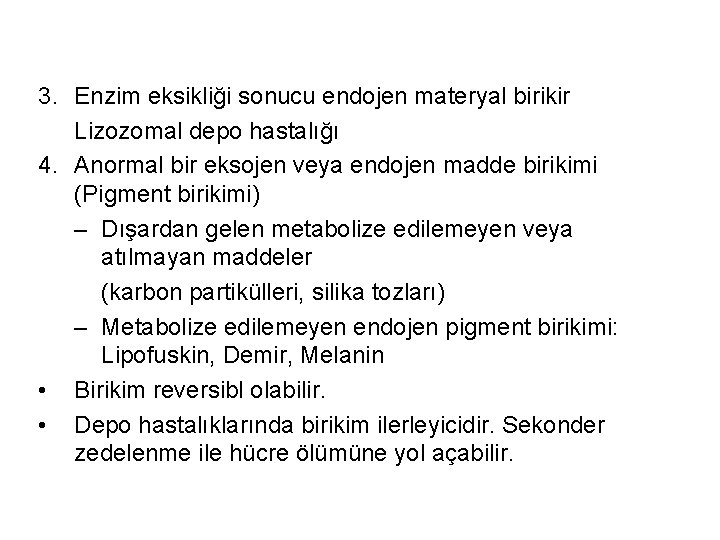

3. Enzim eksikliği sonucu endojen materyal birikir Lizozomal depo hastalığı 4. Anormal bir eksojen veya endojen madde birikimi (Pigment birikimi) – Dışardan gelen metabolize edilemeyen veya atılmayan maddeler (karbon partikülleri, silika tozları) – Metabolize edilemeyen endojen pigment birikimi: Lipofuskin, Demir, Melanin • Birikim reversibl olabilir. • Depo hastalıklarında birikim ilerleyicidir. Sekonder zedelenme ile hücre ölümüne yol açabilir.

lipofuskin hemosiderin